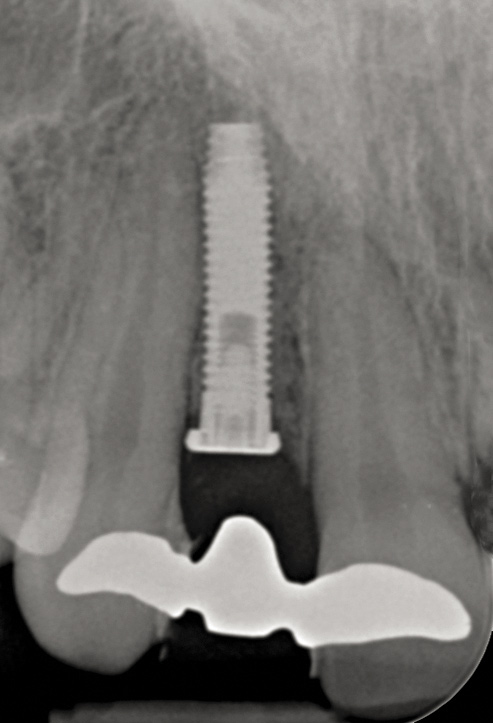

Fig 17. Radiograph showed symmetrical infrabony defect affecting 50% of the implant surface.

Figure 17

Clinical examination showed 2 mm of buccal recession with a shallow vestibule and absence of keratinized attached gingiva against the crown with 8 mm of circumferential pocketing accompanied by bleeding upon probing (Figure 15 and Figure 16). A periapical radiograph showed a symmetrical vertical osseous defect causing the loss of 50% of the bone around the implant (Figure 17). Because the patient had made a significant investment of time and finances to replace her lost tooth with the implant, she desired that the implant and restoration be retained, if feasible.